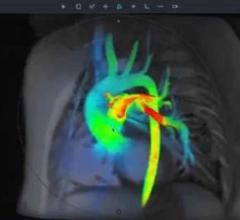

Adopting medical technology because it is new or novel lost its luster a long time ago. It is little wonder then that positron emission tomography/magnetic resonance (PET/MR) has traveled such a bumpy road since the U.S. Food and Drug Administration (FDA) cleared the first PET/MR product in 2011.

In the world of molecular imaging, PET/MR is a wild card. But it’s a wild card that’s ready to be played. Three major vendors offer commercial products. The images are spectacular. So…what’s the hold up?